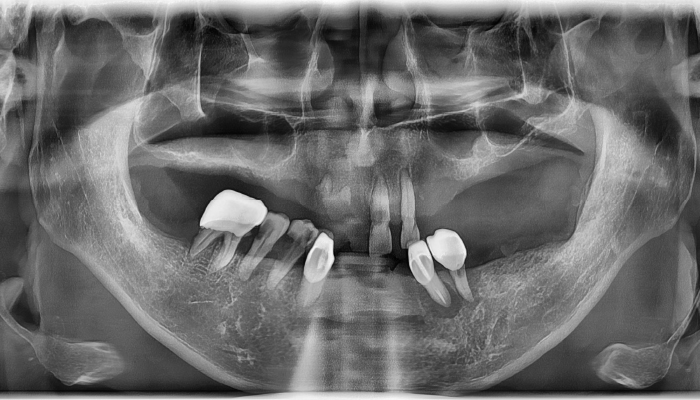

• 식립전

식립후